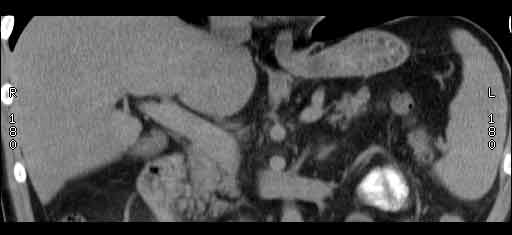

В печени выявлен гипоэхогенный очаг неокруглой формы, аваскулярный при цветовой доплерографии.

Сонограммы, КТ- артериальная, портальная и отсроченная паренхиматозная фазы

Простая и одновременно "сложная" задачка. По УЗИ; явный стеатоз печёночной паренхимы (теперь ключевые слова); на ФОНЕ СТЕАТОЗА определяется гипоэхогенное образование. Варианты? Очаговое образование; и менее вероятно участок гипостеатоза (но не похоже, есть чёткие границе, + не та локализация).

Сделали КТ (весьма похвальная тактика); по КТ: в артериальную фазу: периферическое усиление в виде сливающихся островков контраста, с центрипетальной направленностью. Венозная и отсроченная фаза-хорошее накопление контраста; образование практически изоденсно по отношению к паренхиме печени. Классика гемангиомы. Вуаля-диагноз на "тарелочке".

Вывод: надо иметь ввиду, что эхогенность это относительное понятие, эхогенность гемангиомы может изменятся при изменении положения обследуемого пациента (см. прикреплённую статью); не надо забывать что эхогенность образование это понятие относительное, т.е. относительно окружающей паренхимы печени! При стеатозе, гемангиома может выглядеть гипоэхогенно по отношению к гиперэхогенной паренхиме окружающей печени. И главное, есть сомнение-заказываем таргетное мультифазовое КТ.